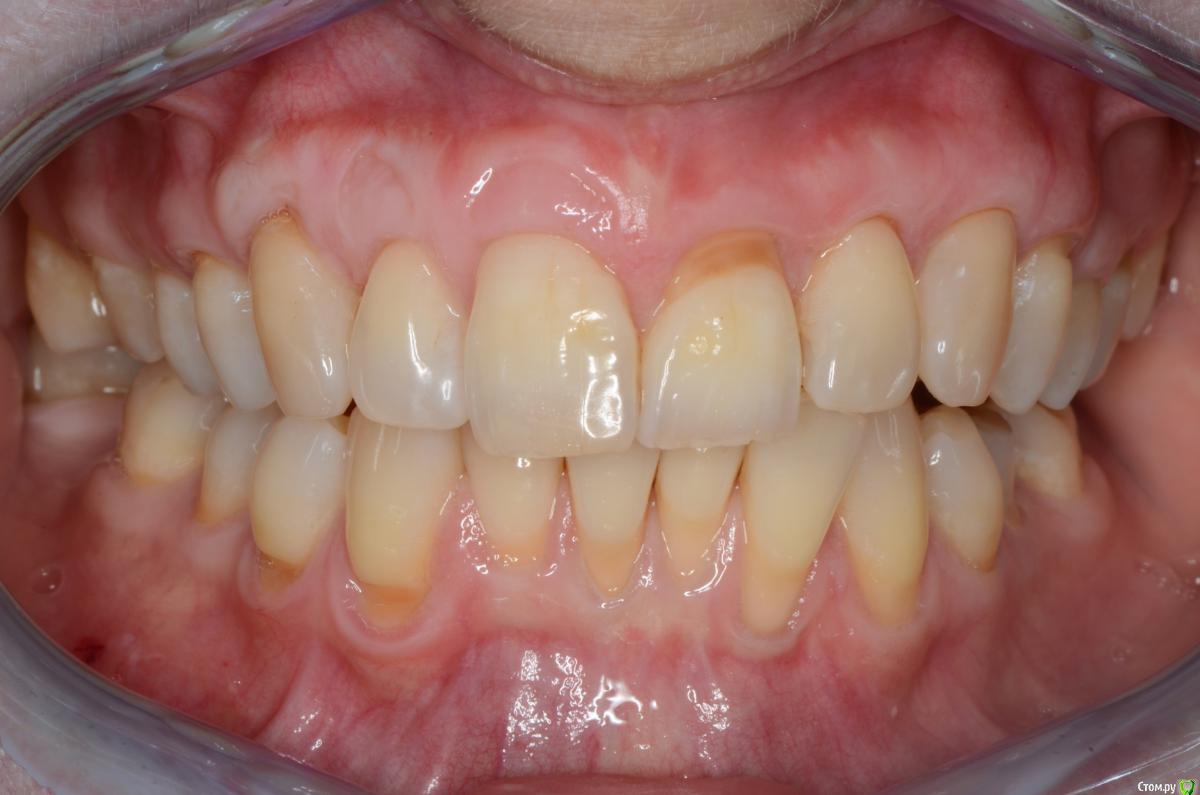

Dmitry DK Опубликовано 31 августа, 2019 Поделиться Опубликовано 31 августа, 2019 Доброго дня! Первичное обращение пациентки было связано с отсутствием 25 зуба, эстетические нарушения слизистой, клиновидные деф-ты в области других зубов - не смущали.В итоге решили, раз проводим операцию ( импл + ССТ ), закроем попутно и рец на верхней челюсти.Реставрацию на 21 зуб все не ставит... Приятных тебе выходных! ) Пациентка проходила лечение 2,5 года назад, пришла на проф осмотр 7 Ссылка на комментарий

Dmitry DK Опубликовано 4 сентября, 2019 Автор Поделиться Опубликовано 4 сентября, 2019 короткий зуб, что же еще.У имплантата край дёсны действительно корональнее.Платплатформа в двух миллиметрах от цементо-эмалевой границы, была возможность иссечь излишек либо его ещё отдавить, также как хотелось заполировать в 1-м сегменте, поставит реставрацию на 21-м и т.д.Пациентка отказалась от дальнейших этапов... Ссылка на комментарий